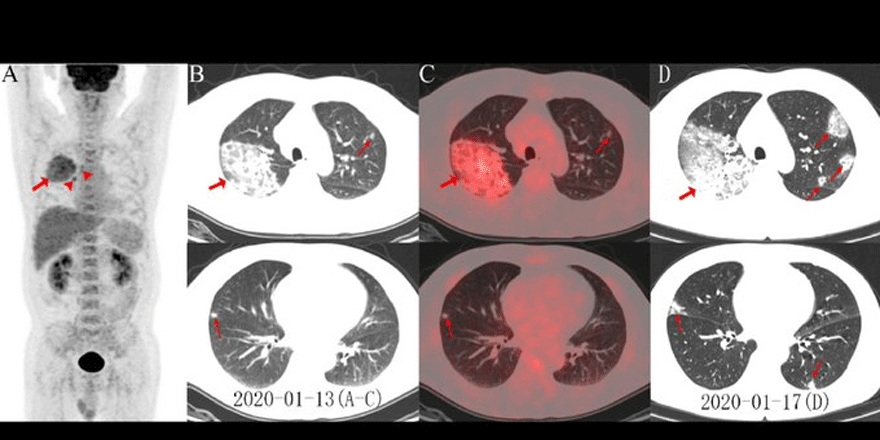

Kuzey Amerika Radyoloji Derneği (RSNA) 44 yaşında corona virüsten ölen bir erkek vakanın akciğer röntgen fotoğraflarını yayınladı.

Röntgen filmlerinde akciğerlerin çevresindeki sıvının nasıl zamanla daha belirgin ve yoğun bir hale geldiğini gözler önüne seriyor.

Visit the @radiology_rsna COVID-19 Special Focus page for newly published images of COVID-19 using FDG PET/CT and images assessing the inflammation burden with volume-rendered chest CT. https://pubs.rsna.org/2019-ncov #CoronavirusOutbreak #CTRad

Çin vatandaşı hastanın yaklaşık iki hafta boyunca ateş ve öksürükten şikayetlerinin ardından sonra 25 Aralık 2019'da hastaneye kaldırıldığı verilen bilgiler arasında. Doktorlar hastada ilk olarak zatürre ve akut solunum sıkıntısı sendromu teşhisinde bulundu.

Hasta tedavi edilmesine rağmen 1 hafta sonra corona virüse bağlı semptomlar nedeniyle yaşamını yitirdi. Corona virüs hastalarının çoğunda ters bir çember işareti belirgin bir şekilde göze çarpıyor. Akciğerlerin alt köşelerindeki beyaz lekeler virüs ün varlığını gözler önüne seriyor.